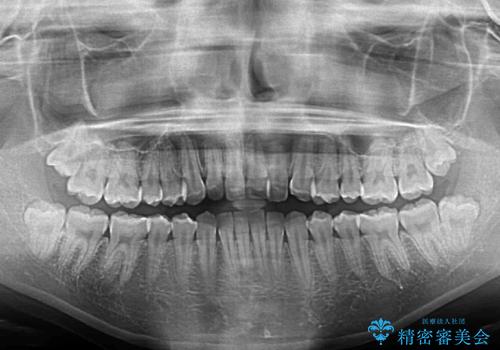

前歯のクロスバイト インビザラインによる矯正治療

- 前歯のクロスバイトを気にして来院された患者様です。

しっかりとインビザラインの装着時間を守っていただいたので、1年弱で矯正治療を終えることができました。